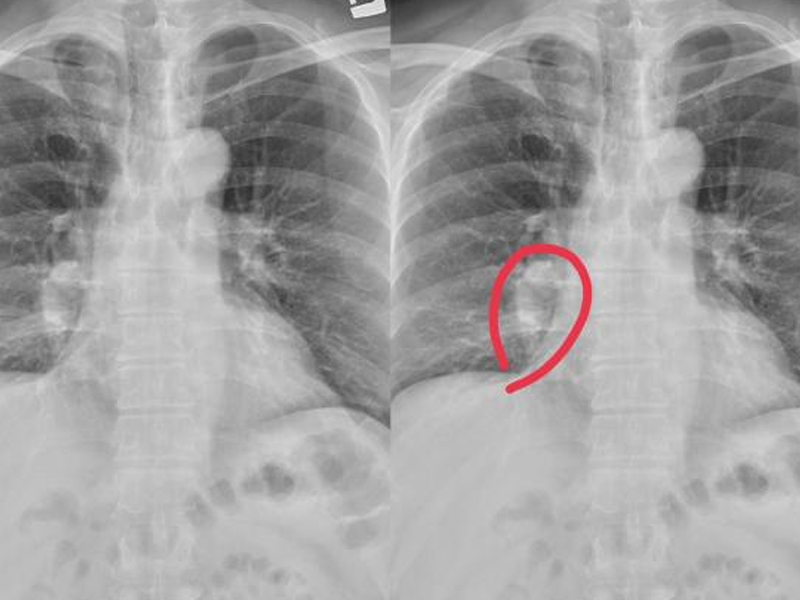

| 胰臟癌被稱為「沈默癌王」,因為其早期症狀並不明顯,容易被忽視。本文將介紹胰臟問題的四個關鍵信號,幫助大家及早識別和預防。 胰臟癌四個關鍵信號 一、上腹部疼痛:不要誤以為是胃痛 胰臟位於胃的後方,當胰臟出現問題時,上腹部會有隱隱的疼痛感。這種疼痛常被誤認為是胃痛,但與胃痛不同,這種疼痛通常不會因為進食或使用胃藥而有所緩解。 二、食慾不振和體重減輕 胰臟癌早期可能會導致食慾不振和無故的體重減輕。這是因為胰臟功能的下降會影響消化系統的運作,導致食物無法正常消化吸收。 三、黃疸症狀 胰臟癌可能壓迫膽管,導致膽汁無法正常排出,引發黃疸。黃疸的典型症狀包括皮膚和眼白變黃,尿液顏色變深,大便顏色變淺。 四、新發糖尿病 研究顯示,胰臟癌患者中有一部分在癌症發現前不久會突然出現糖尿病。這是因為胰臟功能受到損害,導致胰島素分泌異常。 胰臟健康的中醫調理方法 飲食調理:苦瓜和綠茶 苦瓜具有清熱解毒、增強胰臟功能的作用。綠茶中的多酚物質有助於減少胰臟發炎和癌變風險。 穴位按摩:脾俞穴和胰俞穴 中醫認為按摩特定穴位可以促進胰臟健康。脾俞穴位於背部脊柱兩側,按摩此穴位有助於增強脾胃功能,改善消化系統運作。胰俞穴位於腰部,可以通過按摩緩解胰臟壓力,促進胰臟自我修復。 預防胰臟炎的生活習慣 規律飲食和避免暴飲暴食 規律飲食有助於維持消化系統的正常運作,減少胰臟負擔。避免暴飲暴食可以防止胰臟過度工作,減少胰臟發炎的風險。 減少高脂肪和高糖食物攝入 高脂肪和高糖食物容易導致體內脂肪堆積,增加胰臟負擔,甚至引發胰臟發炎。建議多食用新鮮蔬菜水果,保持飲食均衡。 定期健康檢查 定期進行健康檢查,特別是胰臟功能的檢測,可以及早發現胰臟問題,進行及時治療。 胰臟癌的治療效果與早期診斷密切相關。早期發現胰臟癌可以大幅提高治療成功率,減少病情惡化的風險。 |